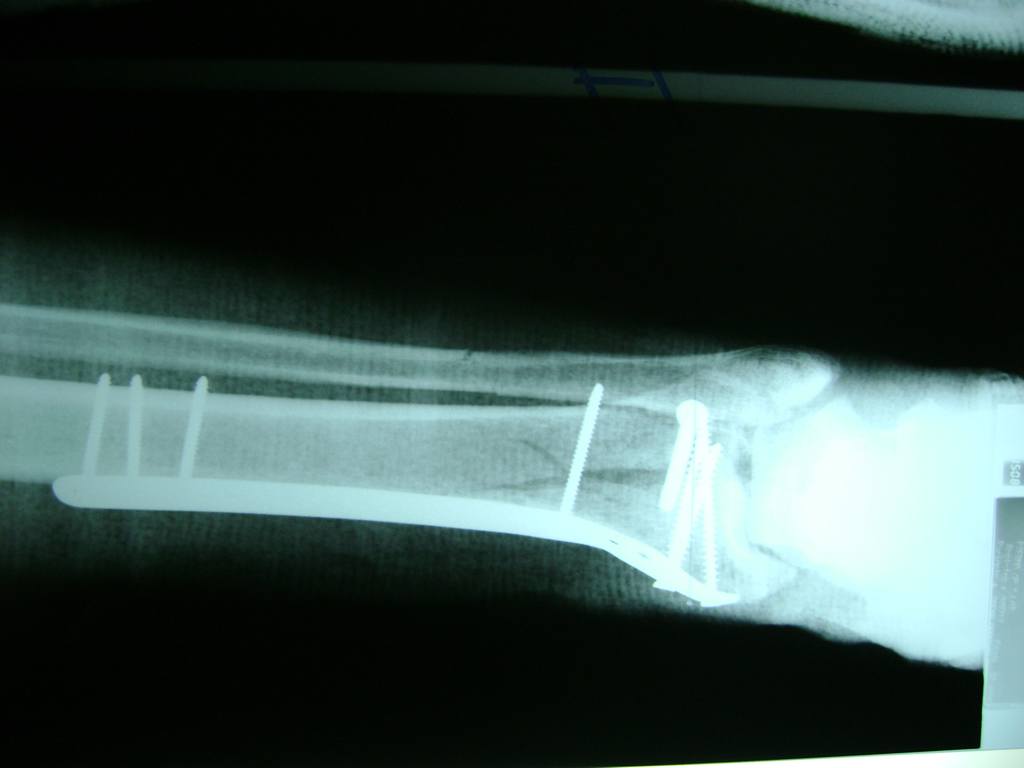

Cuando se necesita cirugía, es probable que esta implique el uso de clavijas de metal, tornillos o placas para sostener los huesos en su lugar mientras la fractura se consolida. Los elementos de soporte pueden ser temporales o permanentes.

Algunas fracturas de tobillo pueden requerir cirugía si:

- El médico cree que sus huesos probablemente no sanen apropiadamente sin cirugía.

- El médico considera que la cirugía puede permitirle una recuperación más rápida y confiable.